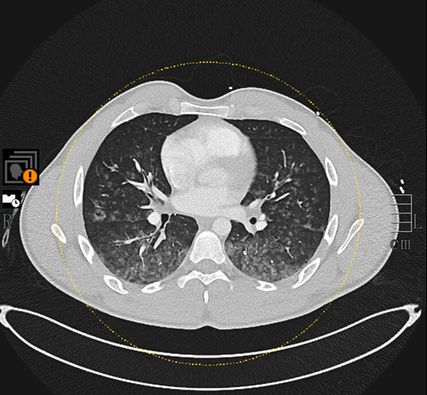

Mittels Pulmonalisangiografie-CT konnte eine Pulmonalembolie ausgeschlossen werden, dafür zeigten sich diffuse und ubiquitär verteilte alveoläre Konsolidierungen (Abb. 1). Eine ältere Bildgebung zum Vergleich lag nicht vor. In Anbetracht der bildmorphologischen Veränderungen wurde unter anderem die Verdachtsdiagnose einer Vaskulitis gestellt.